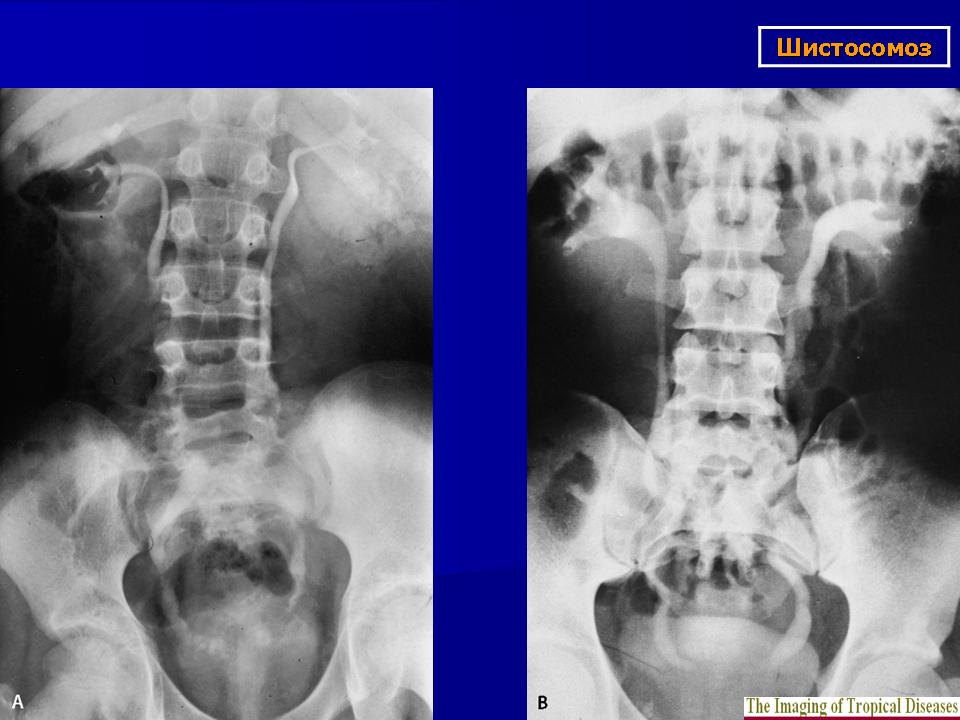

Бильгарциоз (Schistosomiasis) мочевого пузыря